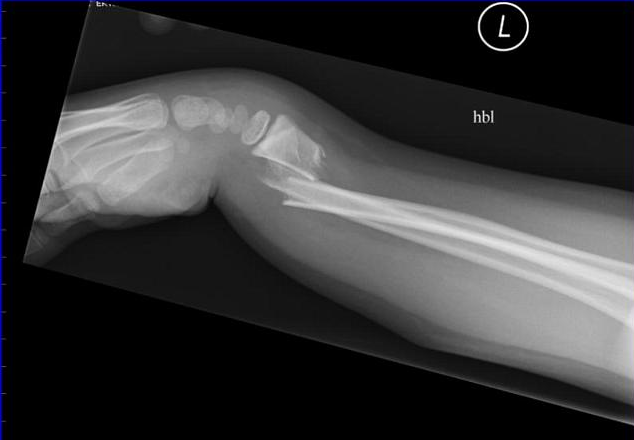

colles fracture

smiths/ reverse colles fracture